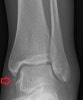

X-ray : 외측 복사뼈 아래의 골편(Lateral malleolus bony fragment)

Cf) 외측 복사뼈 아래의 골편(Lateral malleolus bony fragment)

언젠가 외상으로 avulsion fx일 가능성이 크며, 그 때 떨어졌던 뼛조각이 붙지 않은 채 추후에 발견(실제로는 섬유성결합으로 결합)되었을 가능성이 높습니다.

보통 외측에서 발견되는 예가 흔하며, 내측에서는 드문편입니다.

통증을 일으키지 않는 경우도 많으며 골편에 의해 통증이 있다면 제거하는 것이 치료 방법입니다.